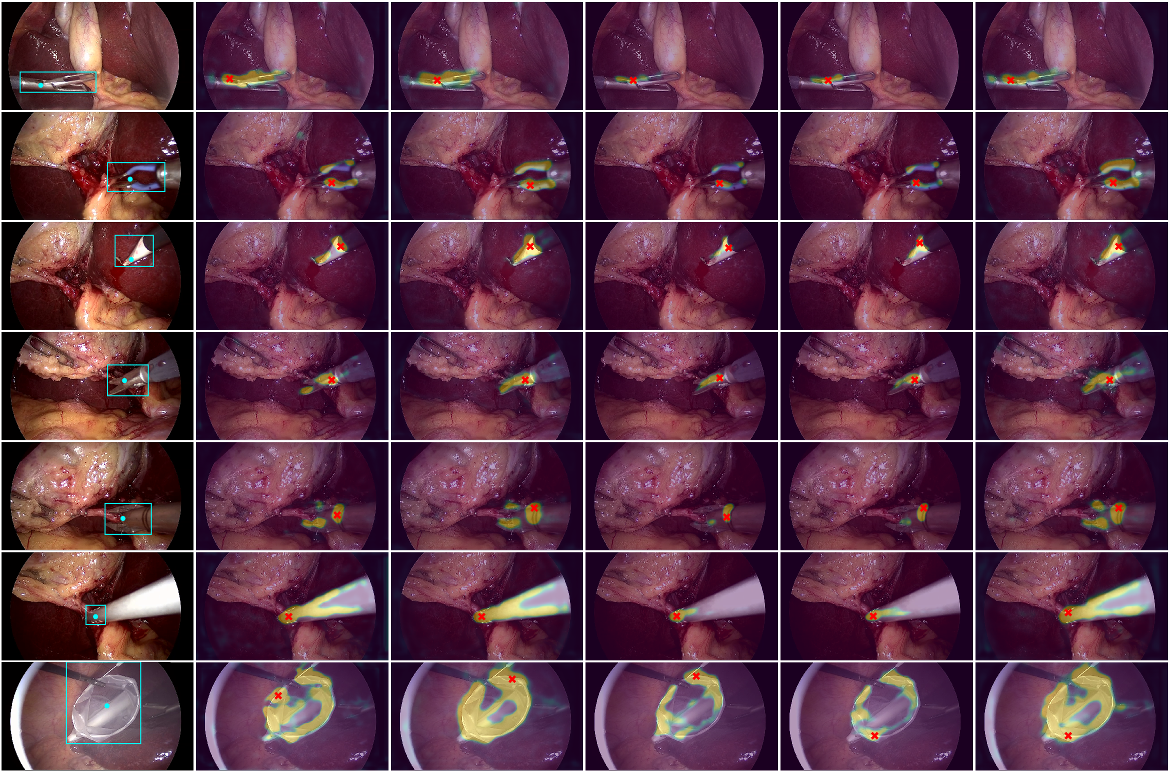

3.4.3 Qualitative Results

For the sake of visual comparison, we present qualitative results for 8 evaluated models in Figure 3, where input images are overlaid with localization maps. Just as the quantitative results suggest, the performances of the networks are very similar and the detected tool centers are very close to one another in most cases. However, the models with masking and ESP generate more detailed maps that cover the tools better than other models and provide strong ROI for the tools.

Refer to caption

Figure 3: Column 1: Ground truth bounding box and tool center. Columns 2-6: input images overlaid with corresponding localization maps (after sigmoid) and predicted tool centers for FCN_ESP, FCN_ESP_Msk, FCN_MSP_Msk, FCN_MSP_MM_Msk, FCN_ESP_MM_Msk, in that order.